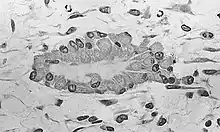

Osteoblastos (do grego ὀστέο-,"osso", e βλαστάνω, "germinar") são as células provenientes das células osteoprogenitoras, são responsáveis pela síntese dos componentes orgânicos da matriz óssea, colágeno, proteoglicanos, glicoproteínas. Os Osteoblastos localizam-se na superfície do osso, formando lâminas de células cuboides a colunares.

Quando estão em intensa atividade sintética, suas formas modificam-se, lembrando um cubo, com citoplasma tornando-se mais basófilo. Em estado pouco ativo tornam-se achatados e a basofilia citoplasmática diminui. Uma vez aprisionado pela matriz óssea recém sintetizada, o osteoblasto recebe o nome de osteócito. A matriz deposita-se em redor da célula e dos seus prolongamentos, formando assim as lacunas e os canalículos (Canais de Havers). Quando os Osteoblastos entram em estado de quiescência, deixam de produzir a matriz, se tornando células de revestimento ósseo.